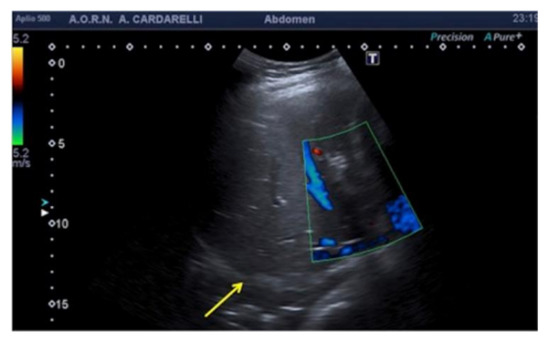

3.1.4. Refraction Artifacts

When the US beam encounters an interface that attenuates the sound to a greater or lesser extent than in the surrounding tissue, the strength of the beam distal to this structure will be either weaker or stronger than in the surrounding field [3]. This occurs because a focus material might cause the beam to deviate from its rectilinear path at an angle that causes a deflection towards the side with the higher resistance (Figure 8). Because this type of artifact can mimic a traumatic kidney rupture, it is recommended that scans are performed with coronal, axial, and sagittal pictures in order to overcome this interpretation deficiency (Figure 9) [5,6].

Figure 9. Coronal images of the left flank. Refraction of the US beam at the lower pole of the spleen causes apparent disruption of the of the middle third of the left kidney (arrows). K: kidney.